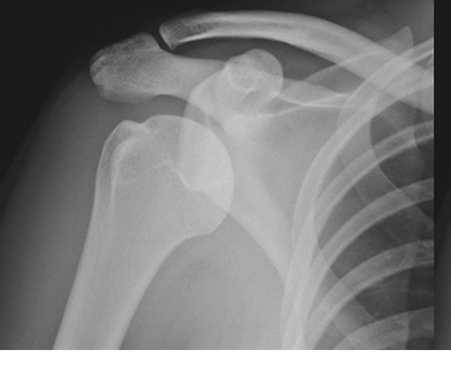

Mastering the Management of Scaphoid Fractures: Avoid Complications

- Scaphoid Fracture: Accurate Diagnosis & Best Treatment Options

- Scaphoid Fractures: Advanced Clinical Guide to Anatomy, Biomechanics, & Management

- Mastering Carpal Fracture Fixation: An Intraoperative Guide to Non-Scaphoid Injuries